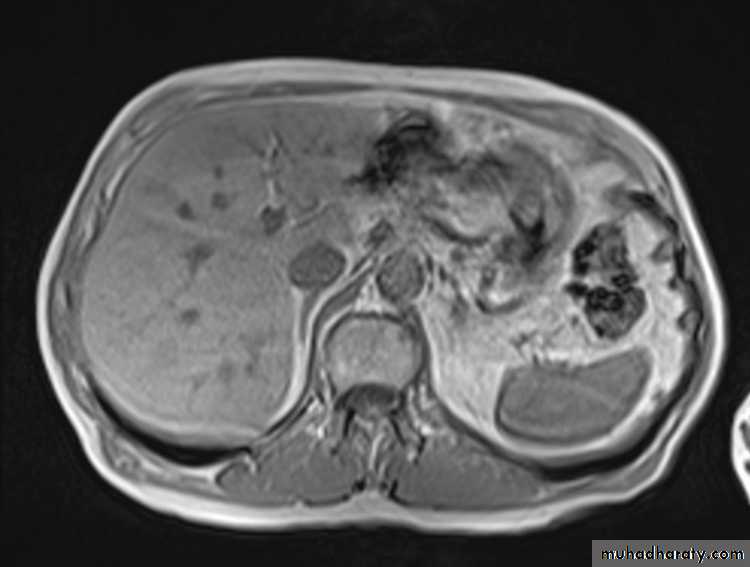

MRI